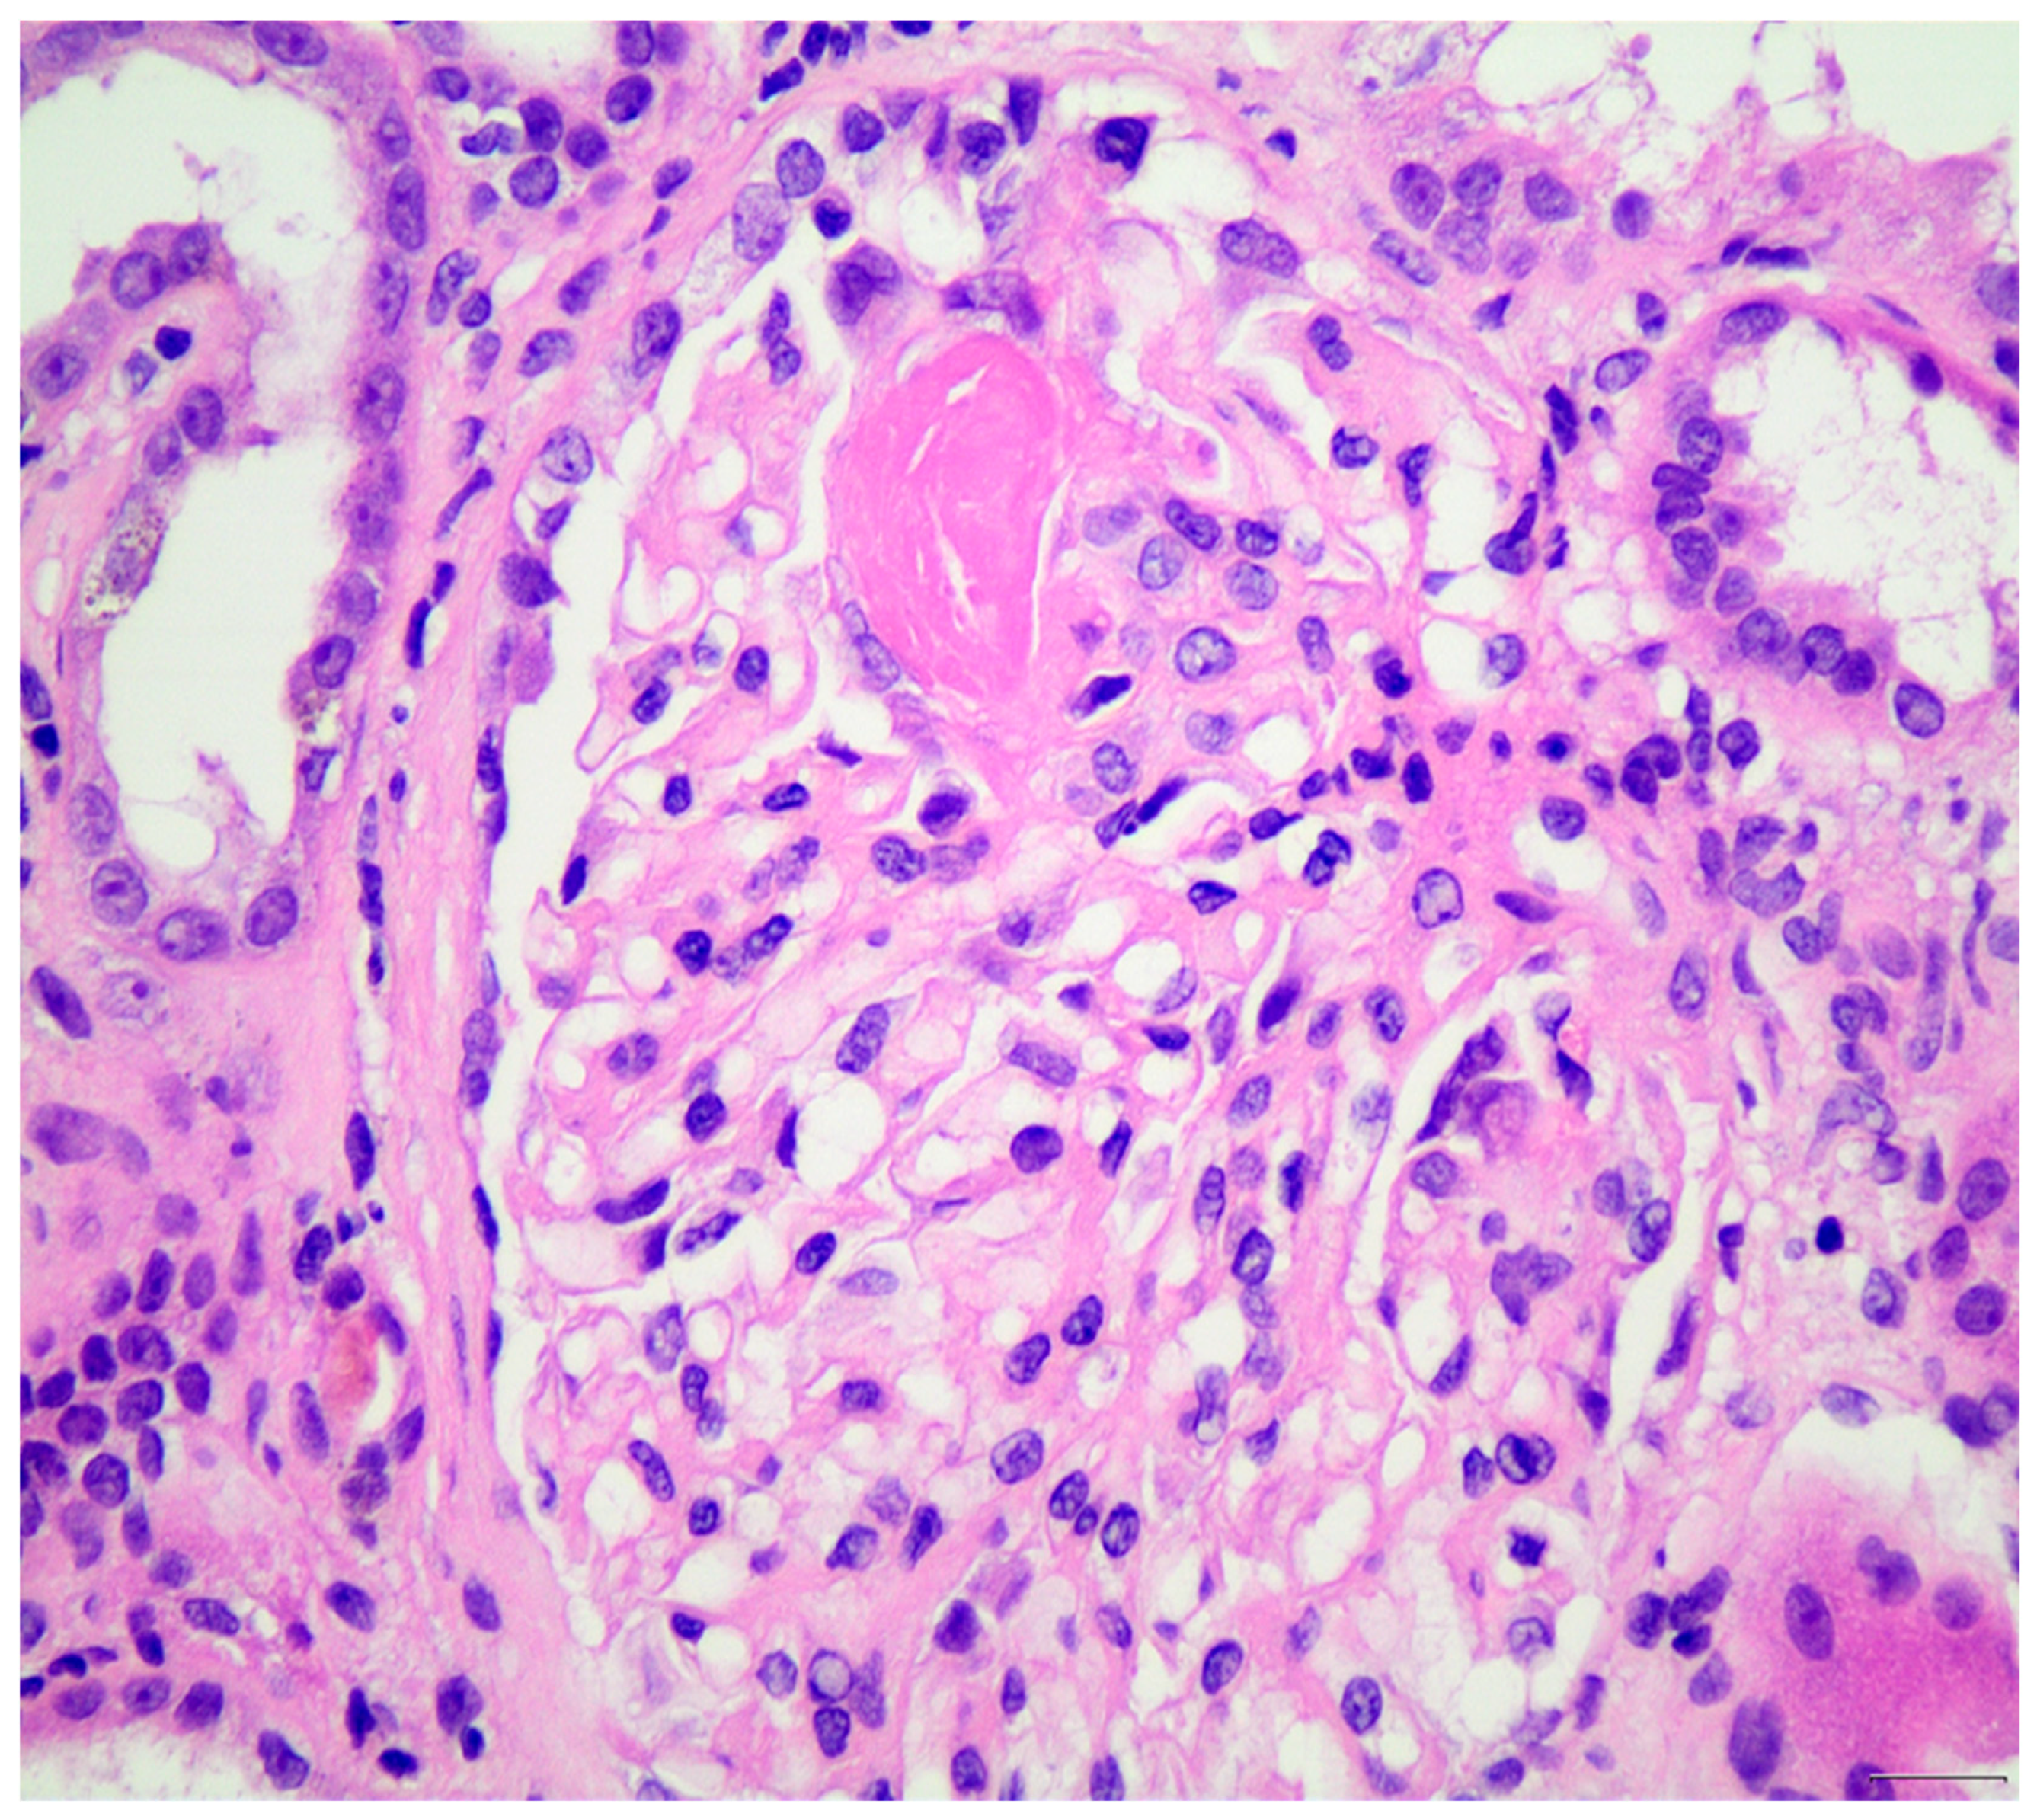

- Hakroush, S.; Tampe, D.; Baier, E.; Kluge, I.A.; Ströbel, P.; Tampe, B. Intrarenal synthesis of complement C3 localized to distinct vascular compartments in ANCA- associated renal vasculitis. J. Autoimmun. 2022, 133, 102924. [Google Scholar] [CrossRef]